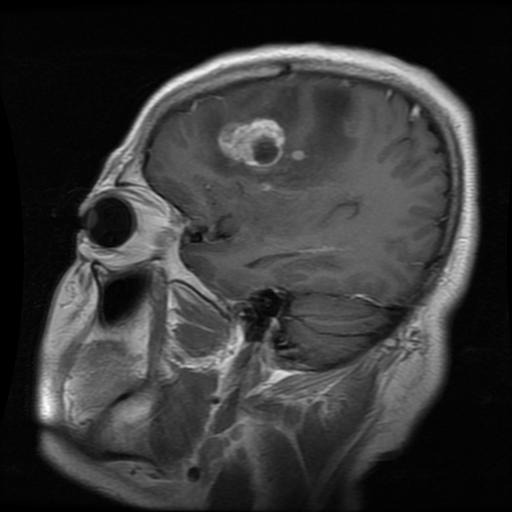

Glioma

Glioma

Glioma

Glioma